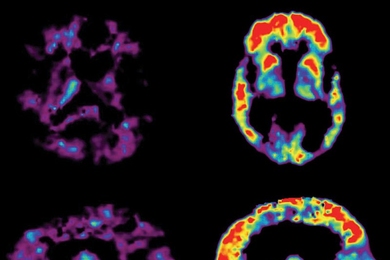

PET Scans Showing PiB Uptake in the brain of a cognitively healthy person (left) and in the brain of a person with AD (right).

MIT neuroscientists are using their knowledge of the brain to generate promising treatments for autism, mental retardation and Alzheimer’s disease.